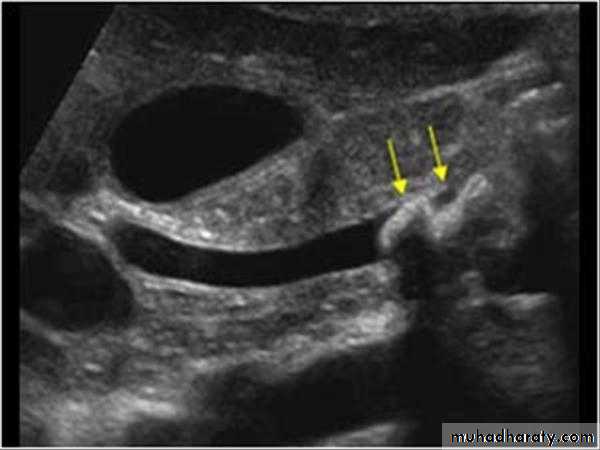

Gall bladder ,biliary tree

CBD not > 7mmnormal intrahepatic tree is too small to seen

• no contrast.Gall stone & cholecystitis

Obstructive jaundice

US

CT

PTC

ERCP & MRCP